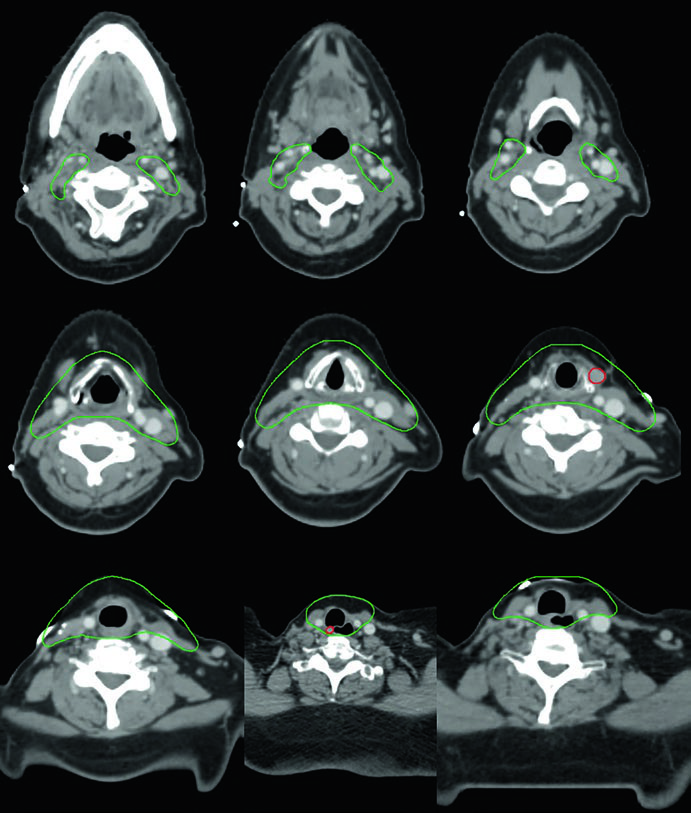

Caso 3 — Anaplásico pós-operatório (Fig. 9.3): Mulher de 50 anos com carcinoma anaplásico submetida a ressecção com extensão extratireoidiana e margens positivas, sem linfonodos envolvidos. Recebeu quimiorradiação pós-operatória. O CTV70 Gy (vermelho) inclui o leito tumoral e os clips cirúrgicos, enquanto o CTV60 Gy (verde) cobre o risco subclínico do compartimento central. A ausência de linfonodos positivos não elimina a necessidade de irradiação subclínica nesse subtipo histológico agressivo — o anaplásico tem taxa de recorrência local e a distância significativamente maior que os diferenciados.

Caso 4 — Recorrência multifocal de variante de células altas (Fig. 9.4): Mulher de 61 anos com variante de células altas do carcinoma papilar, submetida a três cirurgias prévias, que se apresentou com recorrência multifocal. Foi tratada com quimiorradioterapia definitiva. O GTV70 Gy (vermelho) demarca cada foco de recorrência, e o CTV60 Gy (verde) cobre o pescoço subclínico em risco. A variante de células altas é reconhecidamente mais agressiva que a variante papilar clássica, com maior propensão a recorrência e comportamento biologicamente mais adverso.

Quando há recorrência multifocal após múltiplas cirurgias, o campo cirúrgico se torna hostil — fibrose extensa, distorção anatômica e risco aumentado de lesão nervosa tornam nova ressecção proibitivamente arriscada. A quimiorradioterapia definitiva com IMRT permite entregar 70 Gy a cada foco individualmente, com gradiente de dose favorável para os tecidos adjacentes. Cada foco de recorrência exige seu próprio GTV delineado, e o plano precisa acomodar múltiplos alvos de alta dose simultaneamente.